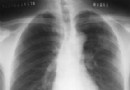

肺結核能引起擴張性心肌病嗎

概 述 結核不會導致擴張性心肌病,結核桿菌除了感染肺導致肺結核,還可以通過血液傳播到骨和腎引起骨結